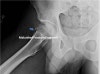

1. X-ray : Hip AP, Lateral view

X-ray : 대퇴골두 골절(Femoral head fracture)